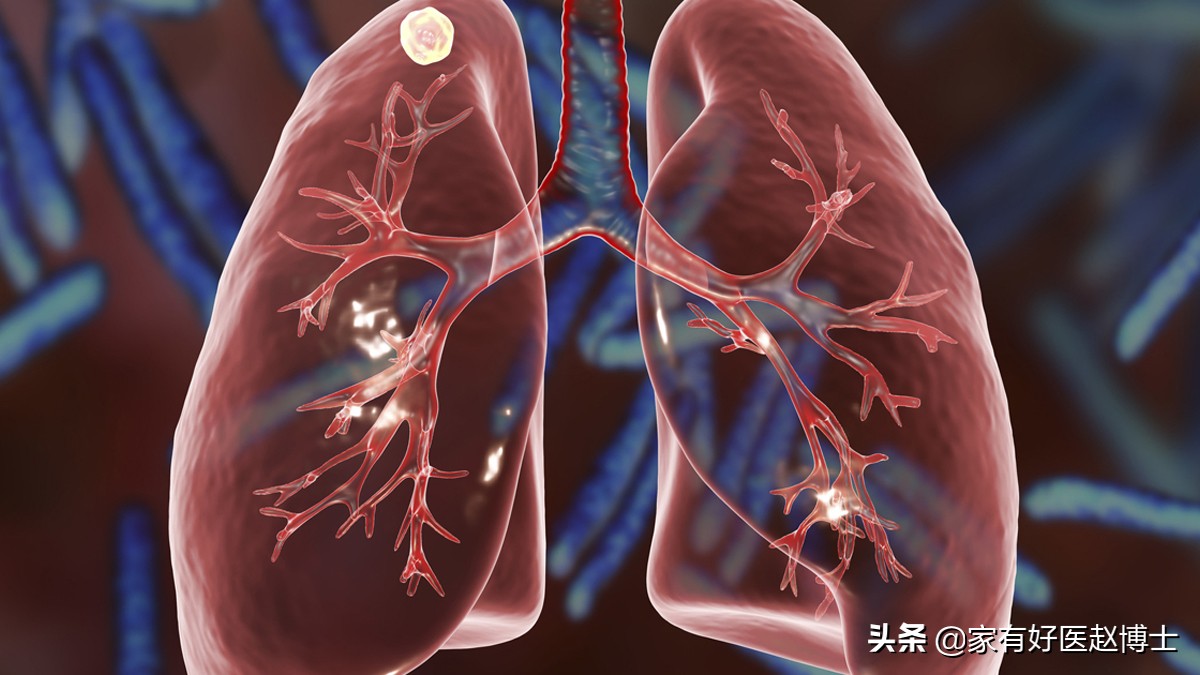

第二个要说的是肺内的钙化灶。这在肺部CT检查的结果当中比较多见,有不少朋友会误以为肺内钙化灶是肺结节甚至肺部肿瘤。但其实,它都不是!

肺内的钙化灶大多是由于以前在这个部位曾经发生过炎症或者损伤,在坏死组织自我修复的过程中逐渐形成的钙化。

在我国,肺内钙化最常见的原因是曾在这个部位发生过肺结核的感染。所以,有些医生看到肺钙化的表现时会问一下:“以前有没有得过肺结核?”当然,除了肺结核以外,肺炎等其他因素也有可能引起肺内钙化。

在大部分情况下,肺内钙化灶属于良性病变,不需要特殊的治疗,定期观察即可。但是,如果肺部CT结果提示,肺内钙化存在于0.8cm以上的肺结节里或在明显的肺部肿块当中,那么,就一定要找胸外科专科医生看一看了。